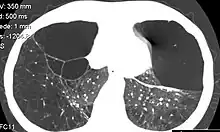

Individuals with A1AD may develop emphysema,[1] or chronic obstructive pulmonary disease during their thirties or forties even without a history of smoking, though smoking greatly increases the risk.[7] Symptoms may include shortness of breath (on exertion and later at rest), wheezing, and sputum production. Symptoms may resemble recurrent respiratory infections or asthma.[8]

A1AT is a glycoprotein mainly produced in the liver by hepatocytes,[9] and, in some quantity, by enterocytes, monocytes, and macrophages.[12] In a healthy lung, it functions as an inhibitor against neutrophil elastase,[13] a neutral serine protease that controls lung elastolytic activity which stimulates mucus secretion and CXCL8 release from epithelial cells that perpetuate the inflammatory state.[14] With A1AT deficiency, neutrophil elastase can disrupt elastin and components of the alveolar wall of the lung that may lead to emphysema, and hypersecretion of mucus that can develop into chronic bronchitis.[15] Both conditions are the makeup of chronic obstructive pulmonary disease (COPD).[16]

Normal blood levels of alpha-1 antitrypsin may vary with analytical method but are typically around 1.0-2.7 g/L.[17] In individuals with PiSS, PiMZ and PiSZ genotypes, blood levels of A1AT are reduced to between 40 and 60% of normal levels; this is usually sufficient to protect the lungs from the effects of elastase in people who do not smoke. However, in individuals with the PiZZ genotype, A1AT levels are less than 15% of normal, and they are likely to develop panlobular emphysema at a young age. Cigarette smoke is especially harmful to individuals with A1AD.[7] In addition to increasing the inflammatory reaction in the airways, cigarette smoke directly inactivates alpha-1 antitrypsin by oxidizing essential methionine residues to sulfoxide forms, decreasing the enzyme activity by a factor of 2,000.